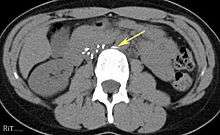

Placement

IVC filters are placed endovascularly, meaning that they are inserted via the blood vessels. Historically, IVC filters were placed surgically, but with modern filters that can be compressed into much thinner catheters, access to the venous system can be obtained via the femoral vein (the large vein in the groin), the internal jugular vein (the large vein in the neck) or the arm veins with one design. Choice of route depends mainly on the number and location of any blood clot within the venous system. To place the filter, a catheter is guided into the IVC using fluoroscopic guidance, then the filter is pushed through the catheter and deployed into the desired location, usually just below the junction of the IVC and the lowest renal vein.[39]

Review of prior cross-sectional imaging or a venogram of the IVC is performed before deploying the filter to assess for potential anatomic variations, thrombi within the IVC, or areas of stenoses, as well as to estimate the diameter of the IVC. Rarely, ultrasound-guided placement is preferred in the setting of contrast allergy, renal insufficiency, and when patient immobility is desired. The size of the IVC may affect which filter is deployed, as some (such as the Birds Nest) are approved to accommodate larger cavae. There are situations where the filter is placed above the renal veins (e.g. pregnant patients or women of childbearing age, renal or gonadal vein thromboses, etc.). Also, if there is duplication of the IVC, the filter is placed above the confluence of the two IVCs [40] or a filter can be placed within each IVC.[41]